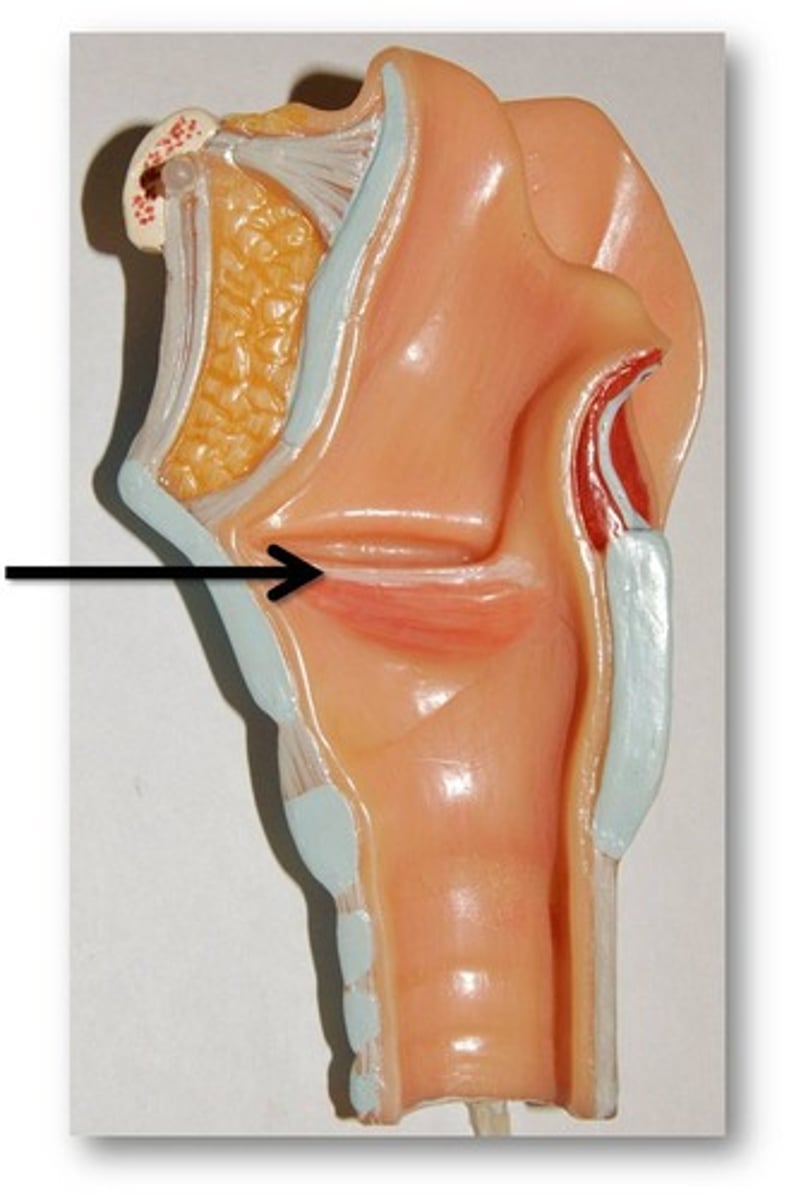

Pharynx

The membrane-lined cavity behind the nose and mouth, connecting them to the esophagus.

Nasopharynx

Region of the pharynx at the back of the nose and above the soft palate

Oropharynx

Central portion of the pharynx between the roof of the mouth and the upper edge of the epiglottis

Laryngopharynx

Lower part of the pharynx, just below the oropharyngeal opening into the larynx and esophagus

Vocal Folds

Mucosal folds that function in voice production (speech); also called the true vocal cords.

Epiglottis

A flap of cartilage at the root of the tongue, which is depressed during swallowing to cover the opening of the windpipe